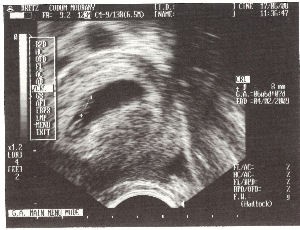

Dneska jsem bylo po prvé u pana doktora, který si mě prohlížel a dokonce mě vyfotil :o) Ještě jsem ale docela malé, měřím teprve 8mm a na obrázku jsem v tom rozmezí dvou křížků, kterými mě pan doktor označil. To světlé malé "nic" v té černé "slzičce"...

A tady už se můžete podívat, co bych mělo mít v tuto dobu všechno vyvinuté. Podle pana doktora bych se mělo narodit až za hooodně dlouhou dobu! Prý až 29.1.2009! To jsem zvědavé, co takovou dobu budu v týhle vodě dělat… Od tohoto dne jsem s maminkou zůstalo doma odpočívat. Mamince je pořád špatně a zvrací několikrát denně a taky v noci